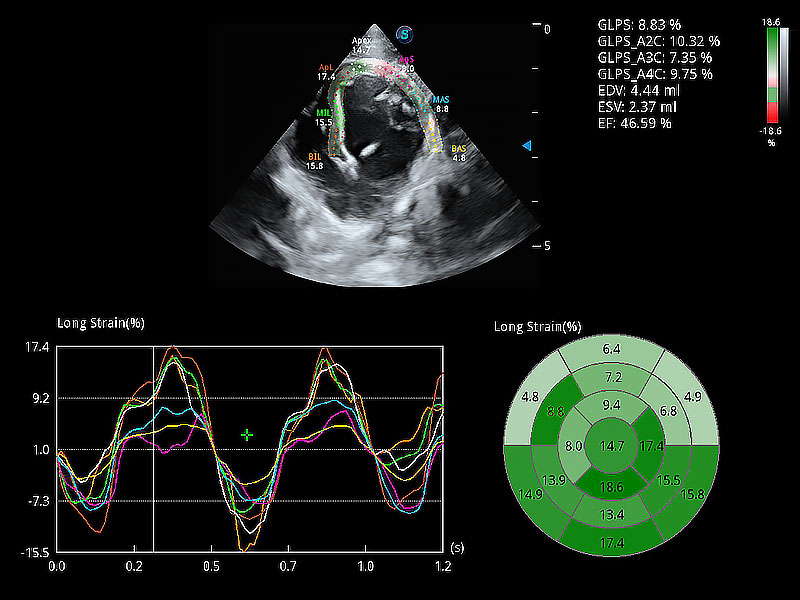

通過心肌識別技術(shù)與二維斑點追蹤技術(shù)相結(jié)合,對心臟的超聲圖像進行量化分析。計算心肌17個節(jié)段的應變、應變率、速度、位移等,并通過牛眼圖的形式進行呈現(xiàn)。